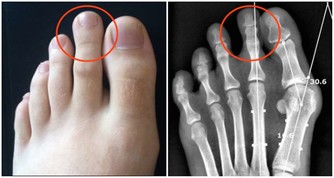

別的一些疾病也會合併口腔潰瘍,比如萊特爾綜合徵、白塞氏病、腫瘤等等疾病會伴發口腔潰瘍。

6. 一些嚴重的疾病,例如白塞氏病和口腔內的惡性腫瘤,此時往往遷延不愈,且可能伴隨全身其它症狀。